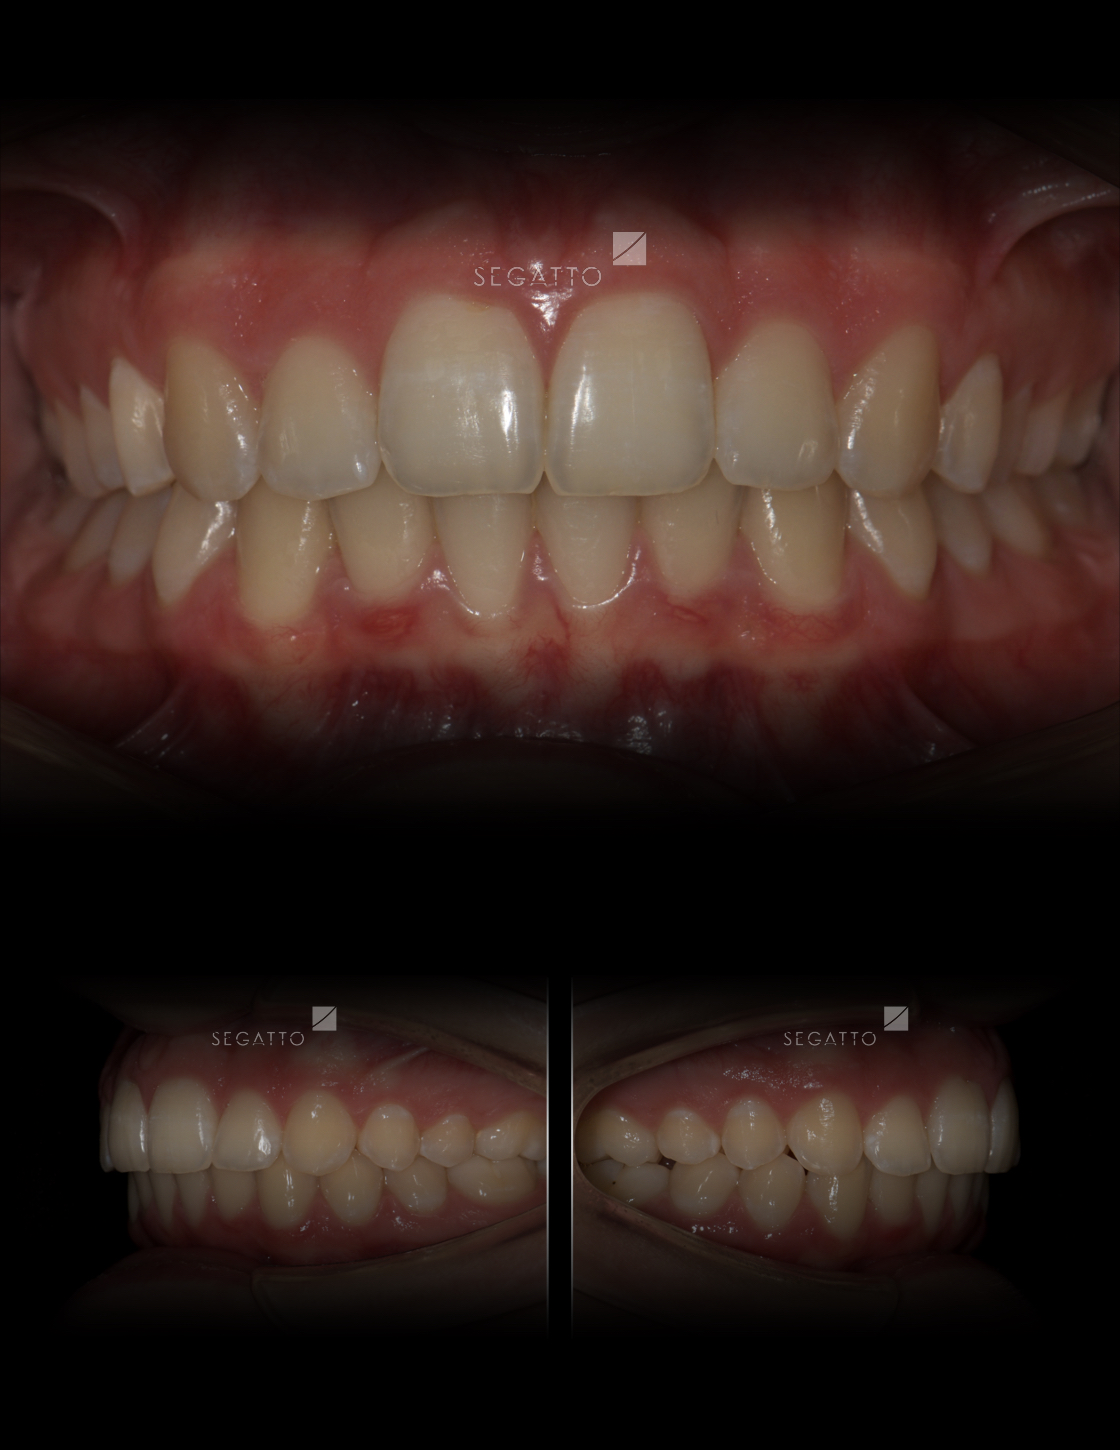

Orthodontics

Cases